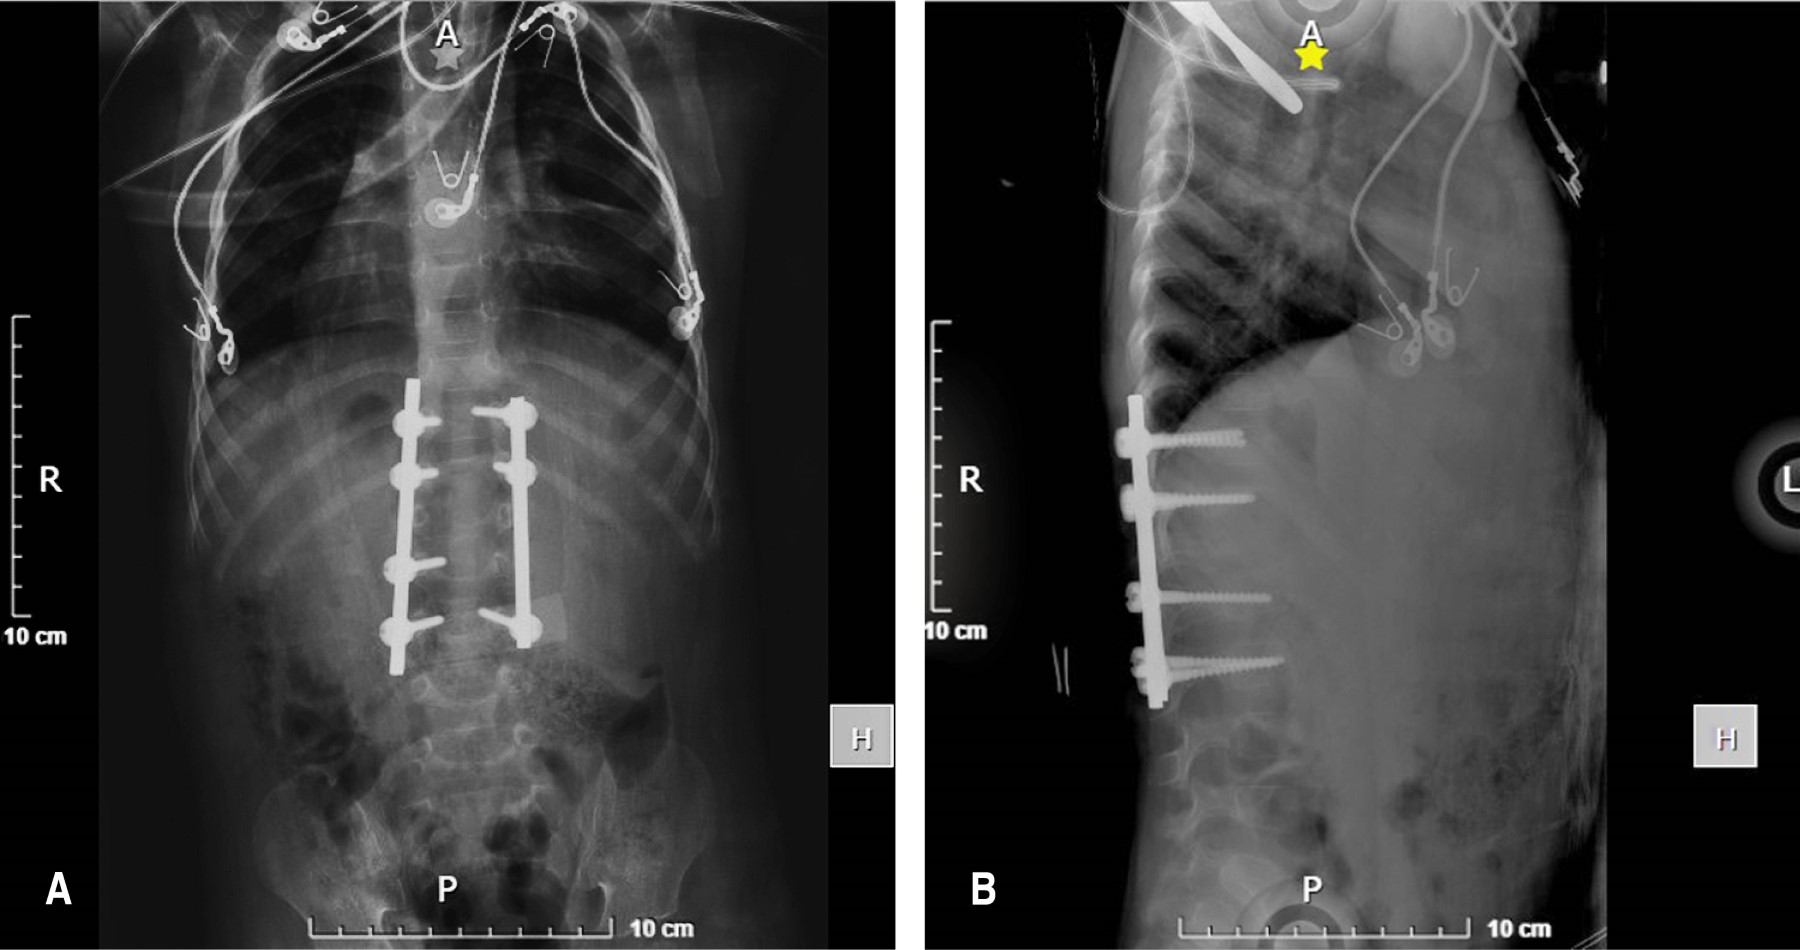

Ante la pobre mejoría clínica con el tratamiento conservador durante dos meses, se realizan rayos X (Figura 3) y resonancia magnética nuclear de control (Figura 4), donde se identificó permanencia del colapso vertebral, compresión de elementos neurales y extensión de la colección hacia la región prevertebral y los músculos iliopsoas bilaterales, con cambios en la intensidad de señal a nivel medular sugestivos de mielopatía en el área afectada. Se realiza intervención quirúrgica mediante instrumentación posterior toracolumbar de T12 a L3, hemilaminectomía izquierda en T12-L1 y drenaje de abscesos con obtención de 3 cc de líquido de aspecto purulento en el espacio T12-L1 y alrededor de 8 cc en la región del psoas derecho (Figura 5 y 6).

El paciente egresó del hospital a las 72 horas postquirúrgicas, cumpliendo con protocolo antimicrobiano y analgésico correspondiente, con adecuado control hemodinámico y seguimiento multidisciplinario por consulta externa con citas periódicas. Cada mes (durante los primeros seis meses) y cada dos meses (durante otros seis meses), con buena evolución: sitio quirúrgico con bordes bien afrontados, sin datos clínicos de infección o dehiscencia, con marcha independiente y no claudicante, miembros pélvicos con fuerza muscular 5/5 y sensibilidad 2/2. En la primer radiografía de control al mes de postquirúrgico se observó corrección de cifosis, material de osteosíntesis sin datos de solicitación ni aflojamiento (Figura 7). Se indicó uso de corset de toracolumbar bivalvado de manera permanente durante al menos 18 horas al día por 12 meses y mantuvo una terapia de tratamiento antifímico bajo supervisión por servicio de infectología pediátrica con buena mejoría clínica. Se plantea retirar la instrumentación en unos años para evitar secuelas en el crecimiento axial.